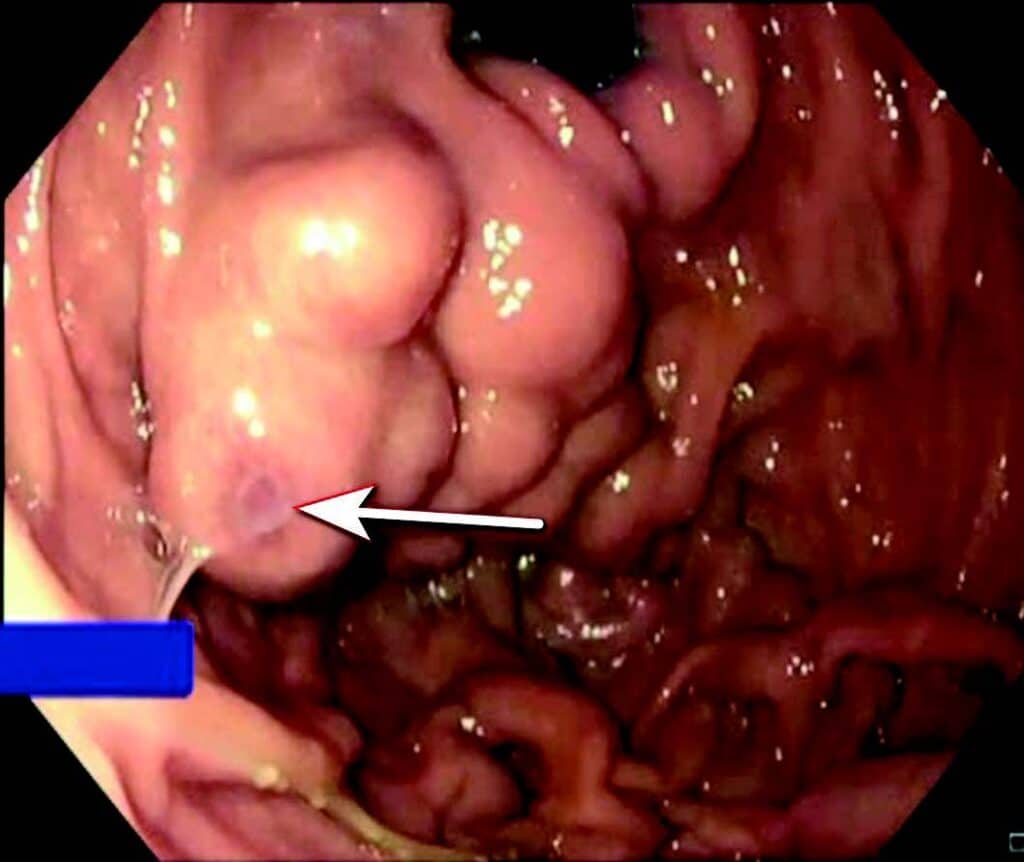

Ved akutt pankreatitt kan kompresjon/obstruksjon og/eller de inflammatoriske forandringene skade splankniske vener, spesielt miltvenen, og føre til trombose. Risiko øker med alvorlighetsgrad av pankreatitten. Ved miltvenetrombose vil ca. halvparten danne gastriske varicer lokalisert i fundus/cardia (Fig 3). Ruptur av varicene kan føre til svært alvorlige blødninger og forekommer hos ca. 7 % av pasienter med slike varicer. Blødende gastriske varicer behandles vanligvis endoskopisk med injeksjon av vevslim (histoacryl) i varicen. Alternativ kan man injiseres en kombinasjon av coiler og lim EUS veiledet i varicene, men denne teknikken er foreløpig lite utbredt. Begge metoder krever erfaring fra både endoskopør og assistenter. Ved manglende endoskopisk ekspertise tilgjengelig kan blødningen midlertidig kontrolleres med ventrikkelballongen på en Sengstaken sonde. Endoskopisk terapi som primærprofylakse mot blødning er oftest ikke indisert.

Fig 3: Gastrisk varice («fundusvarice») hos pasient med miltvenetrombose før endoskopisk liming. Blødning ble midlertidig stanset med Sengstaken sonde og blødningspunktet (fibrinplugg) på varicen er markert med pil.